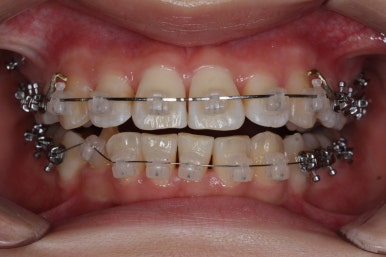

치아는 매우 가지런해졌고, 과개교합도 개선이 되었으며 뻐드러진 앞니 각도도 정상적으로 회복이 되었습니다.

전후사진을 비교해 보겠습니다.

나란히 놓고 보면 차이가 극명하게 납니다.

치아가 가지런해졌습니다.

뻐드러진 앞니가 정상적인 각도로 회복되었습니다.

전반적인 치아들의 위치가 뒤로 이동하였습니다.